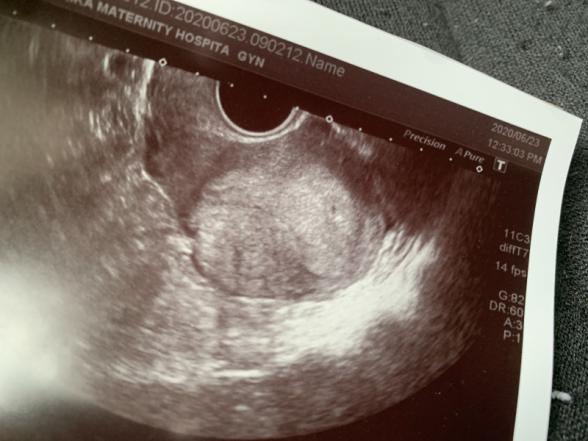

その時のエコーもらったのですが見ていたら左側にもなんかぼやっとした黒いものとその黒いものの周りが白くどちらも2つに囲まれてて、1人目の時にはなかったので双子の可能性とかあるのかな?とか勝手に思ってしまい…

エコーの写真拝見しましたが、ママさんのおっしゃる2つの黒い点が分かりますが、これだけで双胎妊娠、出血層があるとは判断できないです。